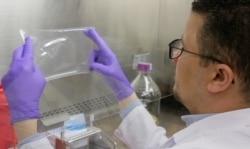

Лаборатории, выращивающие копии ядовитых желез змей, могут заменить змеиные фермы, уверены ученые из Нидерландов, которые вырастили железы одной из самых ядовитых змей – капской коралловой кобры. От яда этой змеи до сих пор нет антидота.

Из желез эмбриона кобры взяли стволовые клетки, обрабатывали "коктейлем" гормонов и факторами роста.

Через неделю стволовые клетки образовали структуры, которые можно было разглядеть невооруженным взглядом. Они напоминали везикулы, обнаруженные в настоящих ядовитых железах змеи. Белки, вырабатываемые этими структурами, были биологически активны и очень напоминали компоненты яда живых змей.

Полученные результаты голландских ученых могут помочь с производством новых противоядий, а также с разработкой новых методов лечения на основе яда.